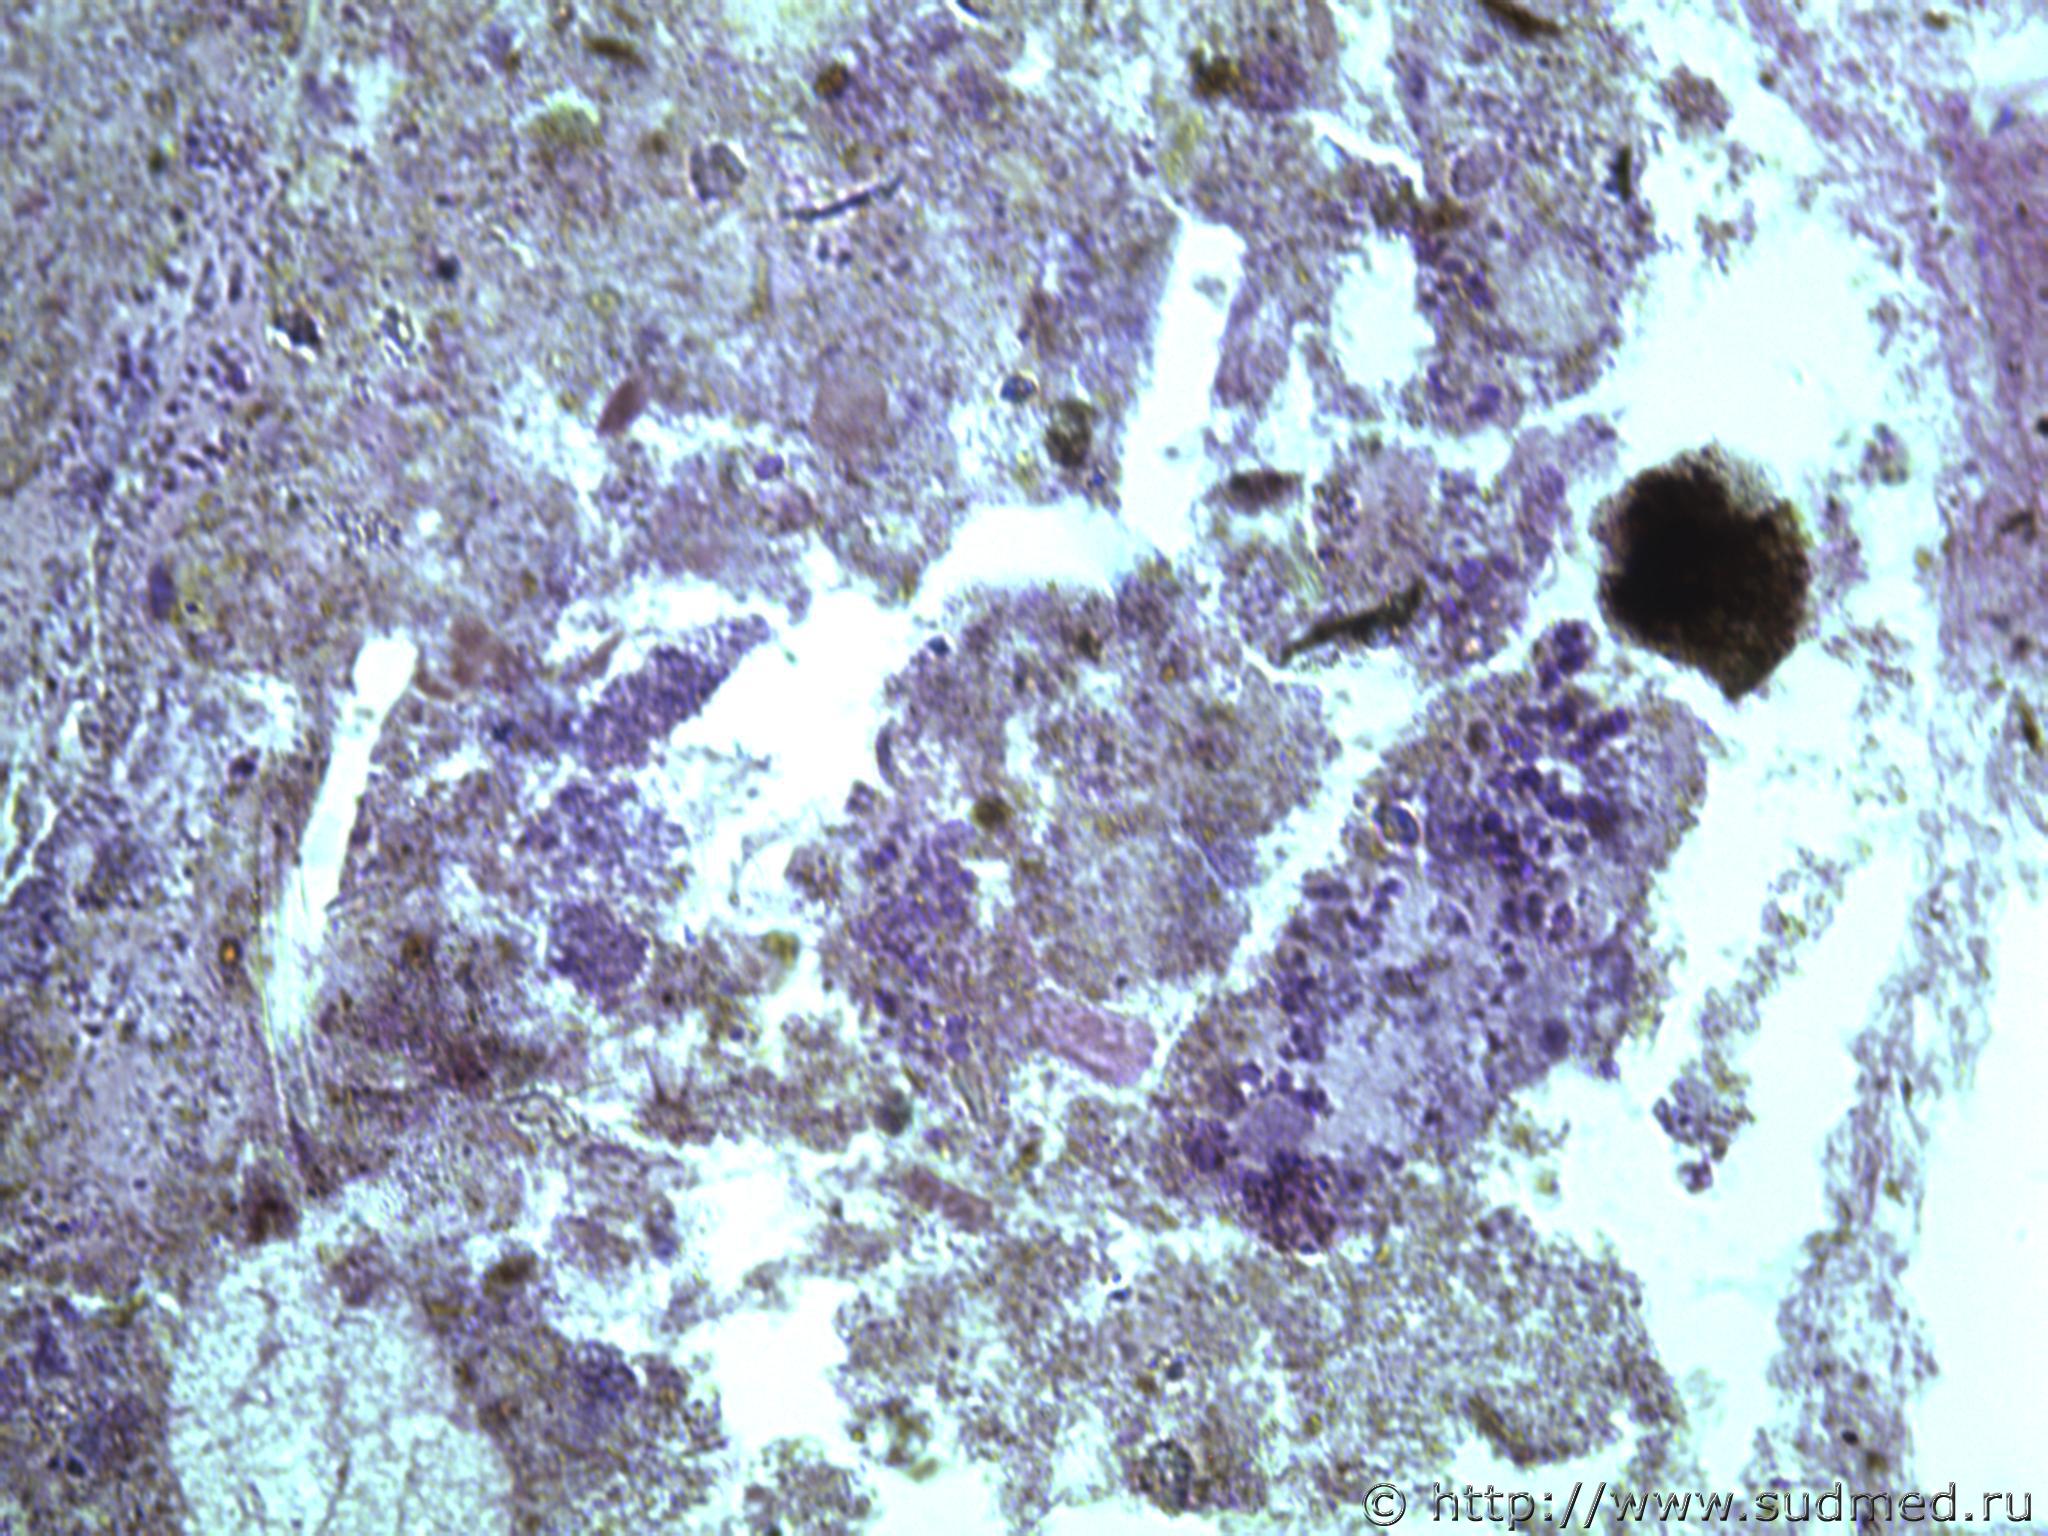

всем здравствуйте. хотела бы знать ваши мнения. провожу экспертизу. препараты как и труп новорожденного гнилые либо в аутолизе страшном. в легком картина такова, что ткань "плотная". просвет различимых альвеол в виде щелей и по всем полям зрения элементы околоплодных вод. одна артерия пуповины спазмирована. остальные сосуды непонятно : просвет их спавшийся но без признаков спазма. они как будто сплющены. да и сама пуповина в виде тонкого тяжа, видно из-за гнилостных изменений. под тмо спинного мозга признаки кровоизлияния, как и в коже с шеи. в коже головы с полнокровием отдельных сосудов. мать утверждает что ребенок после родов не сразу но все же шевелился и кричал. хотя перед этим он выпал у нее из матки на пол, ударившись головой. и со слов матери у него была пена изо рта и он хрипел.

Судебная медицина - Прикрепленное изображение Судебная медицина - Прикрепленное изображениеСудебная медицина - Прикрепленное изображениеСудебная медицина - Прикрепленное изображениеСудебная медицина - Прикрепленное изображение

Плохо,материал гнилой.

Остановился бы на дышавшем лёгком.

5 фото в сообщении №4 и 8 фото в сообщении №5 не наводит ли на мысль о дышавшем лёгком ?

Про остальные фото молчу,там или ничего не видно или же есть оптически пустые пузыри,что вероятнее всего,проявления гниения.